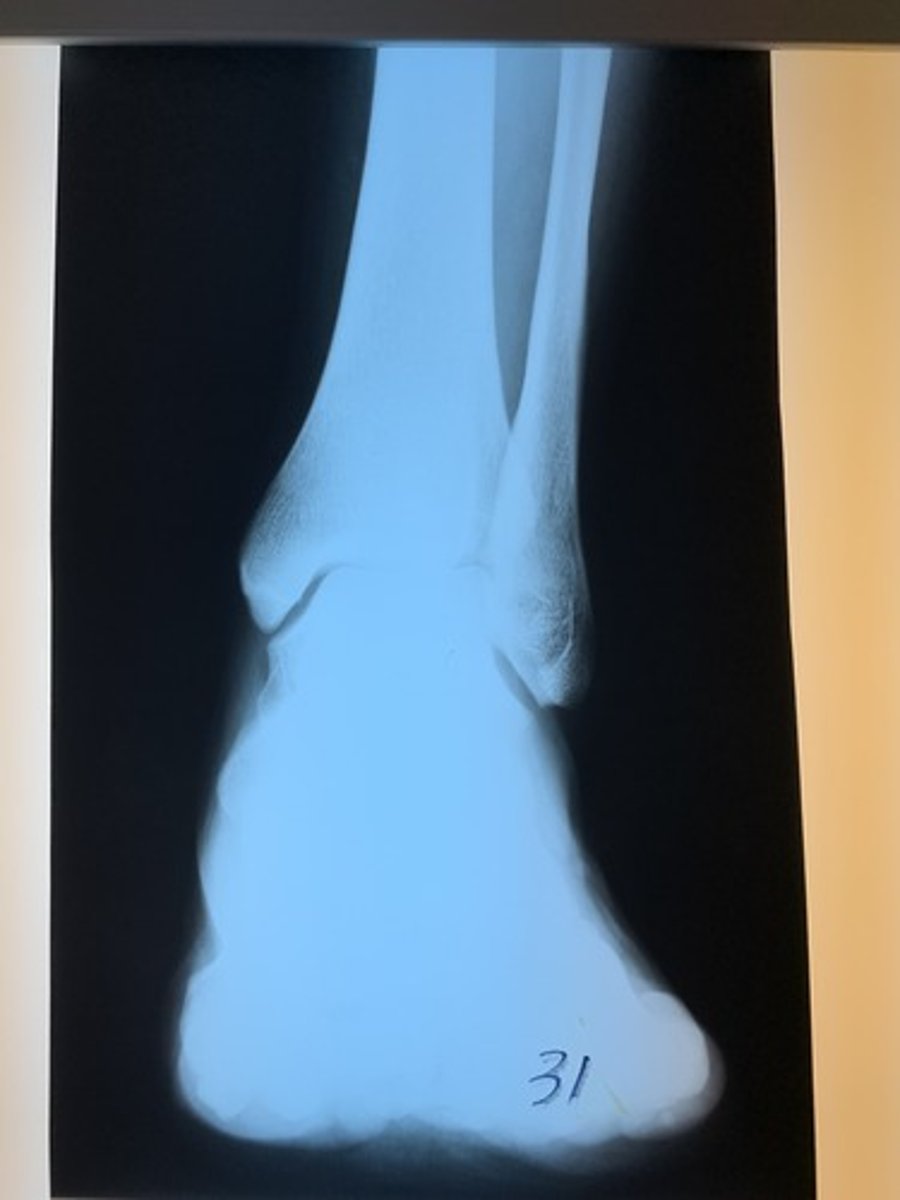

Is radiograph 31 acceptable, underexposed (inadequate mAs), or under-penetrated (inadequate kVp)?

underpenetrated